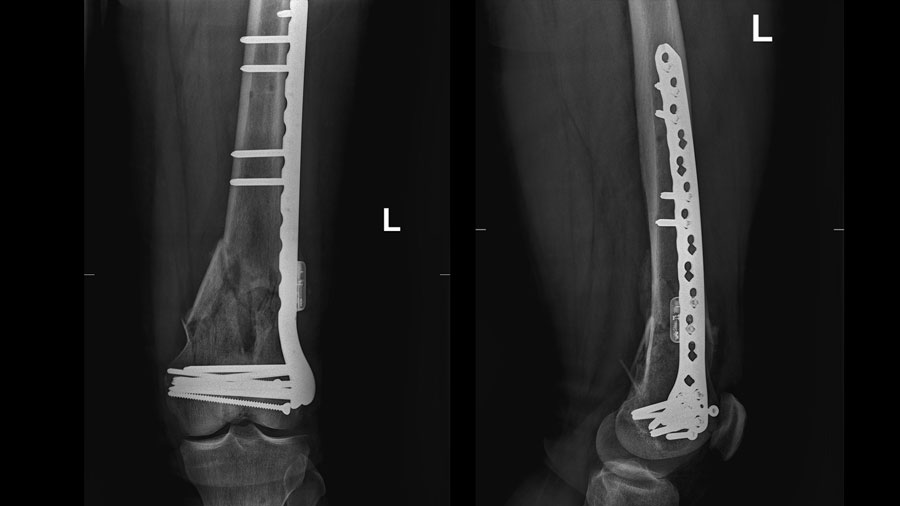

Patient convalescing following first-in-human AO Fracture Monitor application

“The AO Fracture Monitor is revolutionary in that it represents a step away from relying on traditional modalities like x-rays and toward a much more patient specific and accurate ways of monitoring bone healing,” he said. “The AO is helping make this project possible with not only funding but expertise at every step of development. To make a great idea a reality, you need strong partners, and the AO—with the AO Innovation Translation Center, including AO's innovation funding and Clinical Evidence teams, all the way to ARI—is truly a full-service resource.”